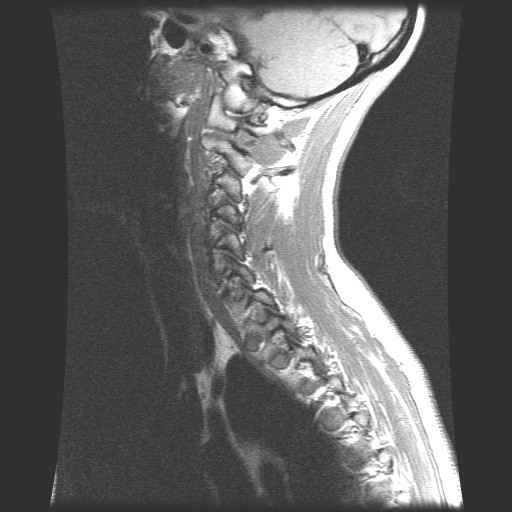

CWZ